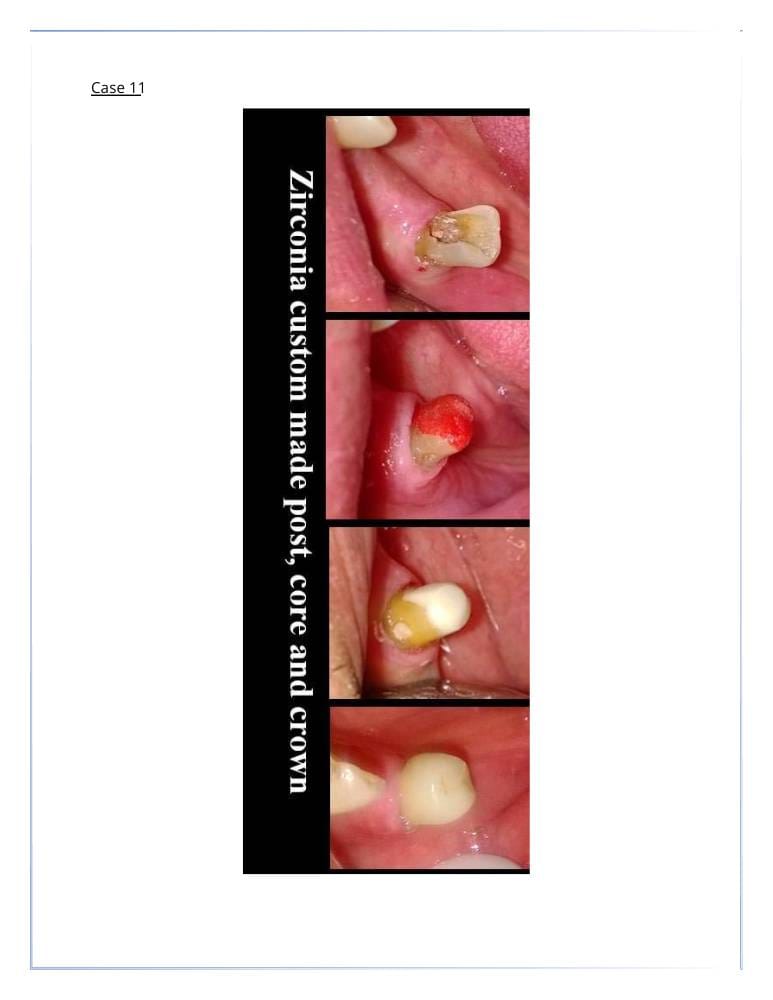

تركيبات الأسنان

- التيجان والجسور الثابتة.

- التركيبات التجميلية لتعويض الأسنان المفقودة.